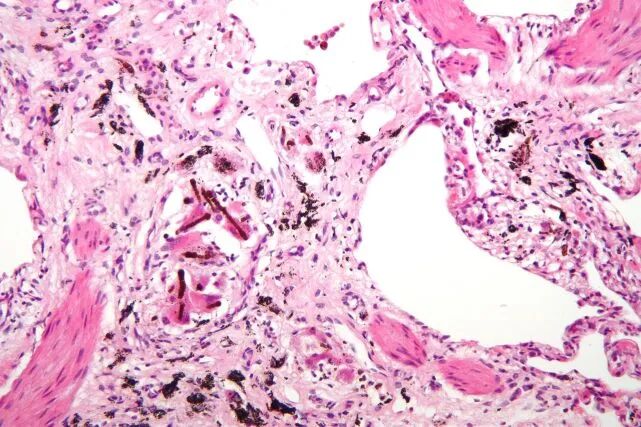

肺部纤维化,源:Nephron

一旦被人体摄入,这些“原纤维”就会堆积在人的肺组织或体内的膜衬里,并逐渐导致细胞死亡,随着时间推移,这个过程就会引发癌变。

石棉引发的癌症包括间皮瘤,肺癌,喉癌,卵巢癌等等,由于癌症的引发需要很长时间——有时候可能需要20年之久,所以许多人可能并没有把癌症和石棉相关联。